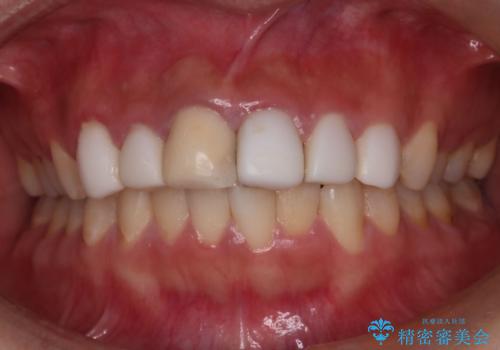

- 他院で治療した前歯の色が気になるということで来院された患者様です。前歯に色の差があり、レントゲンから内部にう蝕も見られたため、審美性に優れ、う蝕になりにくいオールセラミッククラウンで治療いたしました。